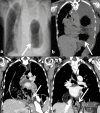

Post-esophagectomy hiatal hernia is a rare complication having varied presentation from asymptomatic cases detected incidentally on follow-up imaging to acute surgical emergency for strangulation or gangrene. Patients presenting as a surgical emergency have a prolonged post-operative course with significant morbidity. We present three cases of post-esophagectomy hiatal hernia. Two of the three cases were operated for esophageal squamous cell carcinoma (SCC) and one patient was operated for esophageal leiomyomatosis. Two of the three cases (SCC and esophageal leiomyomatosis) underwent minimally invasive Mckeown's esophagectomy and one case underwent robotic transthoracic Ivor-Lewis esophagectomy. All cases underwent contrast enhanced CT (CECT) and were biopsy proven prior to their index surgery. Both cases of SCC had prior neoadjuvant chemoradiation followed by surgery while esophageal leiomyomatosis underwent upfront surgery. All three cases have improved symptomatically and are doing well on follow up (case 1 - 12 months, cases 2 and 3 - 3 months). All three of our cases have different clinical presentation in terms of symptoms, severity, and time duration from index surgery. Two of the three cases underwent emergency surgery and one case which was asymptomatic detected incidentally on surveillance imaging and was managed conservatively. Post-esophagectomy hiatal hernia is a rare entity with varying presentation. The management options in such cases vary depending on the severity of symptoms and time after index surgery. In cases presenting as surgical emergency, successful management depends on prompt detection, early surgery, proper post-operative care, and rehabilitation.